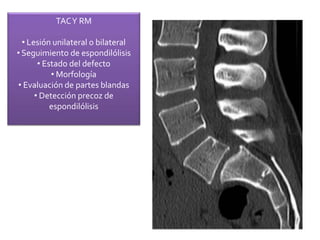

TACY RM

• Lesión unilateral o bilateral

• Seguimiento de espondilólisis

• Estado del defecto

• Morfología

• Evaluación de partes blandas

• Detección precoz de

espondilólisis

TACY RM • Lesiónunilateral o bilateral • Seguimiento de espondilólisis • Estado del defecto • Morfología • Evaluación de partes blandas • Detección precoz de espondilólisis